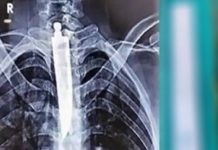

சாப்பிட மு.டியாமல் தி.ண.றி வந்த நபர்..! – ஸ்கேன் ரி.ப்போ.ர்ட்டை பார்த்து ஆ.டி.ப்.போ.ன மருத்துவர்கள்..!

X-ரேயில்........

மத்திய பிரதேசத்தின் சதர்பூர் மாவட்டத்தைச் சேர்ந்த 32 வயதான நபர் ஒருவர் மருத்துவமனையில் அனுமதிக்கப்பட்டுள்ளார். மேலும், அந்த நபர் இரண்டு நாட்களாக தன்னால் எதையும் சாப்பிட மு.டியவில்லை என்றும் வி.ழு.ங்.கும் போது க.டு.மை.யான...